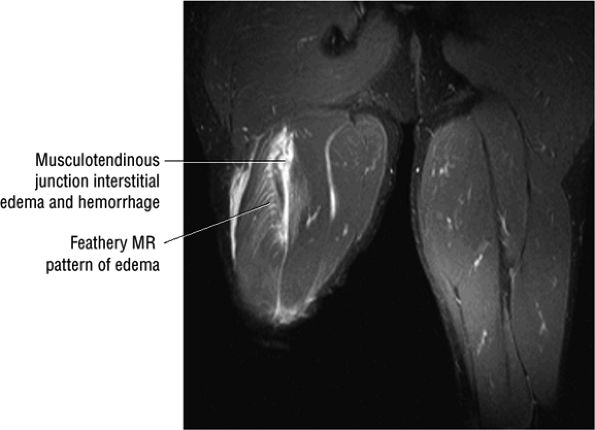

Grade 1: Hyperintense edema with or without hemorrhage and preservation of muscle morphology (Fig. 3.109). On FS PD, T2 FSE, and STIR images there is an edema pattern, displayed as interstitial hyperintensity with a feathery distribution (Fig. 3.110). Hyperintense subcutaneous tissue edema and intermuscular fluid can also be seen.

-

FIGURE 3.110 ● Feathery edema pattern and mild intramuscular fluid (a grade 2 characteristic) in a grade 1 to 2 biceps femoris muscle strain. Coronal FS PD FSE image.